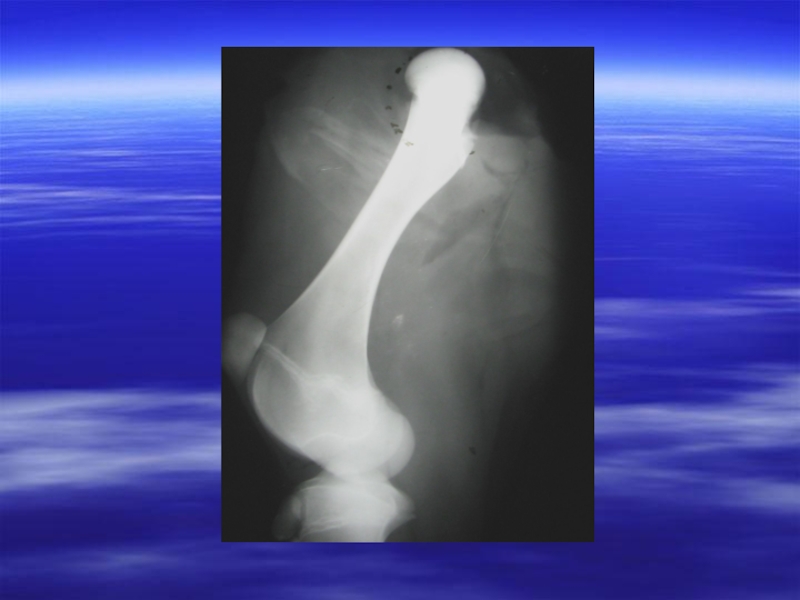

Слайд 8Ұзын жілік сүйегінің диафизінің сынығы, сынған жерде сирақтың қозғалуымен және крепитациямен

бірге жүреді. Ұшы үшкір болып келген сынықтарды қолмен ұстап байқауға немесе зақымданған жердің терісінен көруге болады.

Слайд 9Ашықтану сызығы – сынықтың қиғаш жазығы. Сүйек бұлшық етке қарағанда рентген

сәулесін 250 есе артық сіңіреді. Сынған жердегі сынықтардың арасына қан ұйып қалады, соңынан біріктіргіш және остеоидтік ұлпа пайда болады. Бұл жерлерден рентген сәулелері сүйек көлеңкесіне ашық сызықтар қалдырып, еркін өтеді.

Слайд 10 Ж ы л ж у к ө л е

ң к е с і. Өлшемі мен қарқындығылығына қарай жылжу көлеңкесі әртүрлі болады. Ірі және жуан сынықтарда көлеңке жылжуы айқындалған және рентген суретке түсірген кездегі проекцияға байланысты, сүйек жиектерінің алдыңғы, артқы, бүйірлі беткейлерінен шығып тұрады.